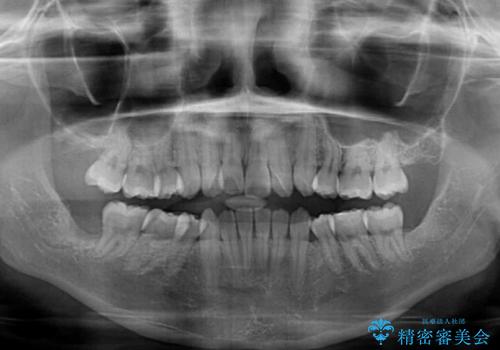

- 抜歯矯正の後戻りを気にして来院された患者様です。

舌の突出癖によるオープンバイトになっていたため、インビザラインによるマウスピース矯正をおすすめしましたが、自己管理の自信がないとのことで、ワイヤー装置による矯正治療を行うこととしました。

舌の突出癖が認められると、上下前歯の隙間を閉じることができません。

舌のトレーニングをしっかりと行っていただくことで、歯列を整えることができます。